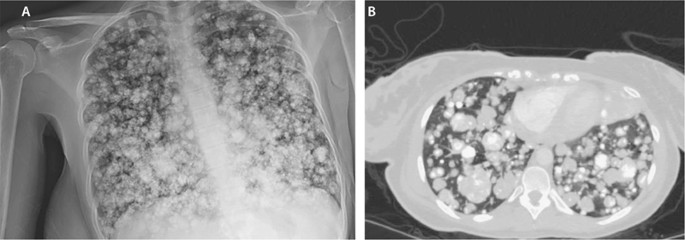

Lungenmetastasen sind Tochtergeschwülste eines außerhalb oder auch in der Lunge selbst entstandenen Ursprungstumors. In der Mehrzahl der Fälle sind sie ein Hinweis auf eine Streuung des Tumors im ganzen Körper. Manchmal bereiten Lungenmetastasen unklare Beschwerden wie Husten Kurzatmigkeit oder Brustschmerzen oft aber sind sie symptomlos und werden zufällig zum Beispiel bei einer Röntgenaufnahme des Brustkorbs oder bei der Nachsorge einer Krebserkrankung.

Lungenmetastasen entstehen wenn sich Tumorzellen von bösartigen Tumoren in anderen Organen ablösen und in der Lunge ansiedeln. Lungenmetastasen sind Krebsgeschwulste die sich von einem anderen Tumor in die Lunge ausgebreitet haben.